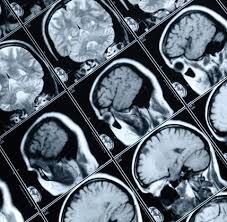

Efecto de las estatinas en los resultados funcionales neurológicos en pacientes adultos críticos con lesión cerebral traumática: revisión sistemática y metanálisis

No se encontraron pruebas concluyentes que apoyen el uso de estatinas en pacientes adultos críticos con TCE en este momento. Sin embargo, los ensayos fueron limitados y los intervalos de confianza amplios dieron lugar a una incertidumbre significativa de los hallazgos. No se puede descartar un beneficio potencial, lo que subraya la necesidad de un ensayo más grande y bien diseñado. BMJ Open, 19 de febrero de 2025

Las patologías mixtas, incluyendo la encefalopatía traumática crónica, explican la demencia en los futbolistas de fútbol

Acta Neuropathologica, 15 de febrero de 2016 Esta pequeña serie de casos publicada en Acta Neuropathologica sugiere que los futbolistas parecen estar en riesgo de encefalopatía traumática crónica (ETC).

Seguridad de la TC diferida en los pacientes alcoholizados atendidos en Emergencias con posible lesión cerebral traumática